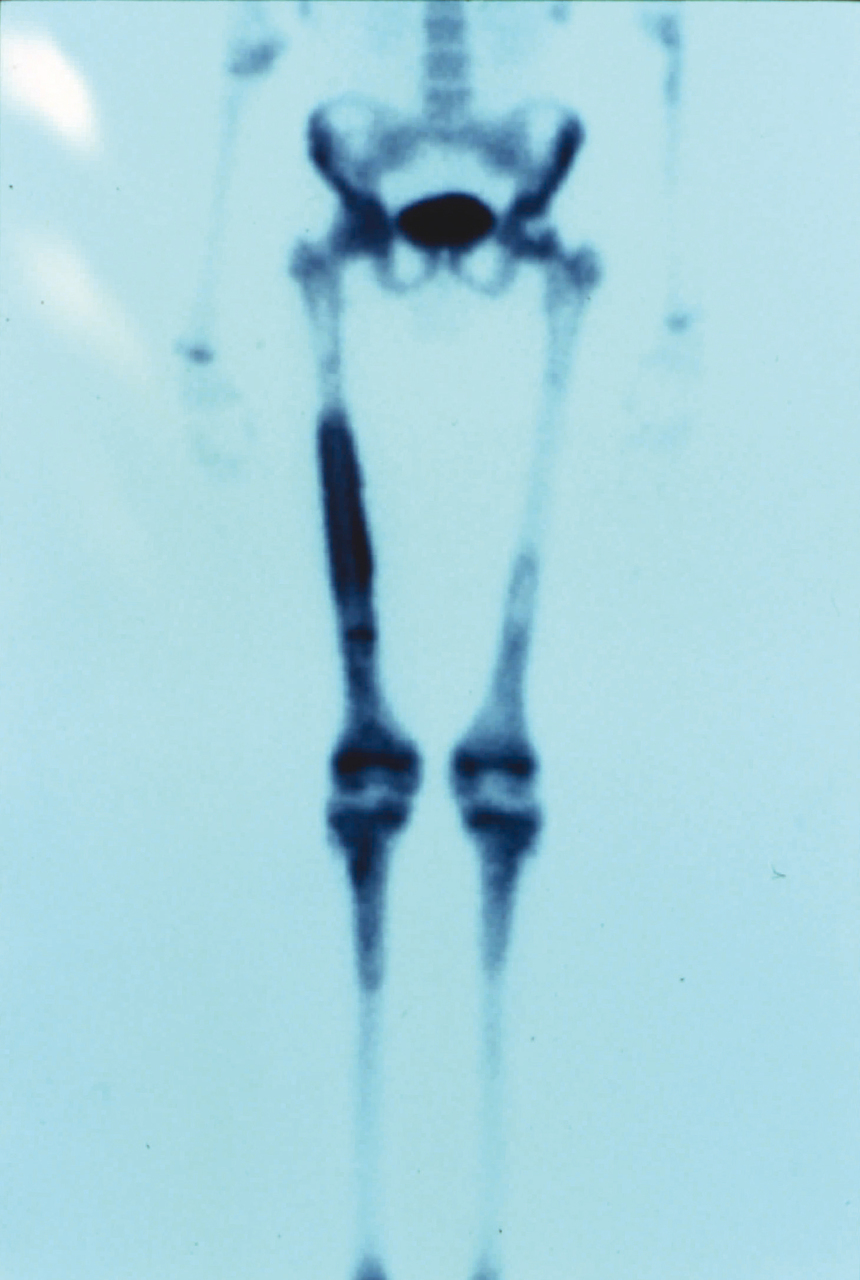

Quel est votre diagnostic ? Ostéomyélite Il s'agit d'une ostéomyélite. Périartérite noueuse Ostéoarthropathie hypertrophiante pneumique Algodystrophie Maladie d'Erdheim-Chester OK Valider mes réponses